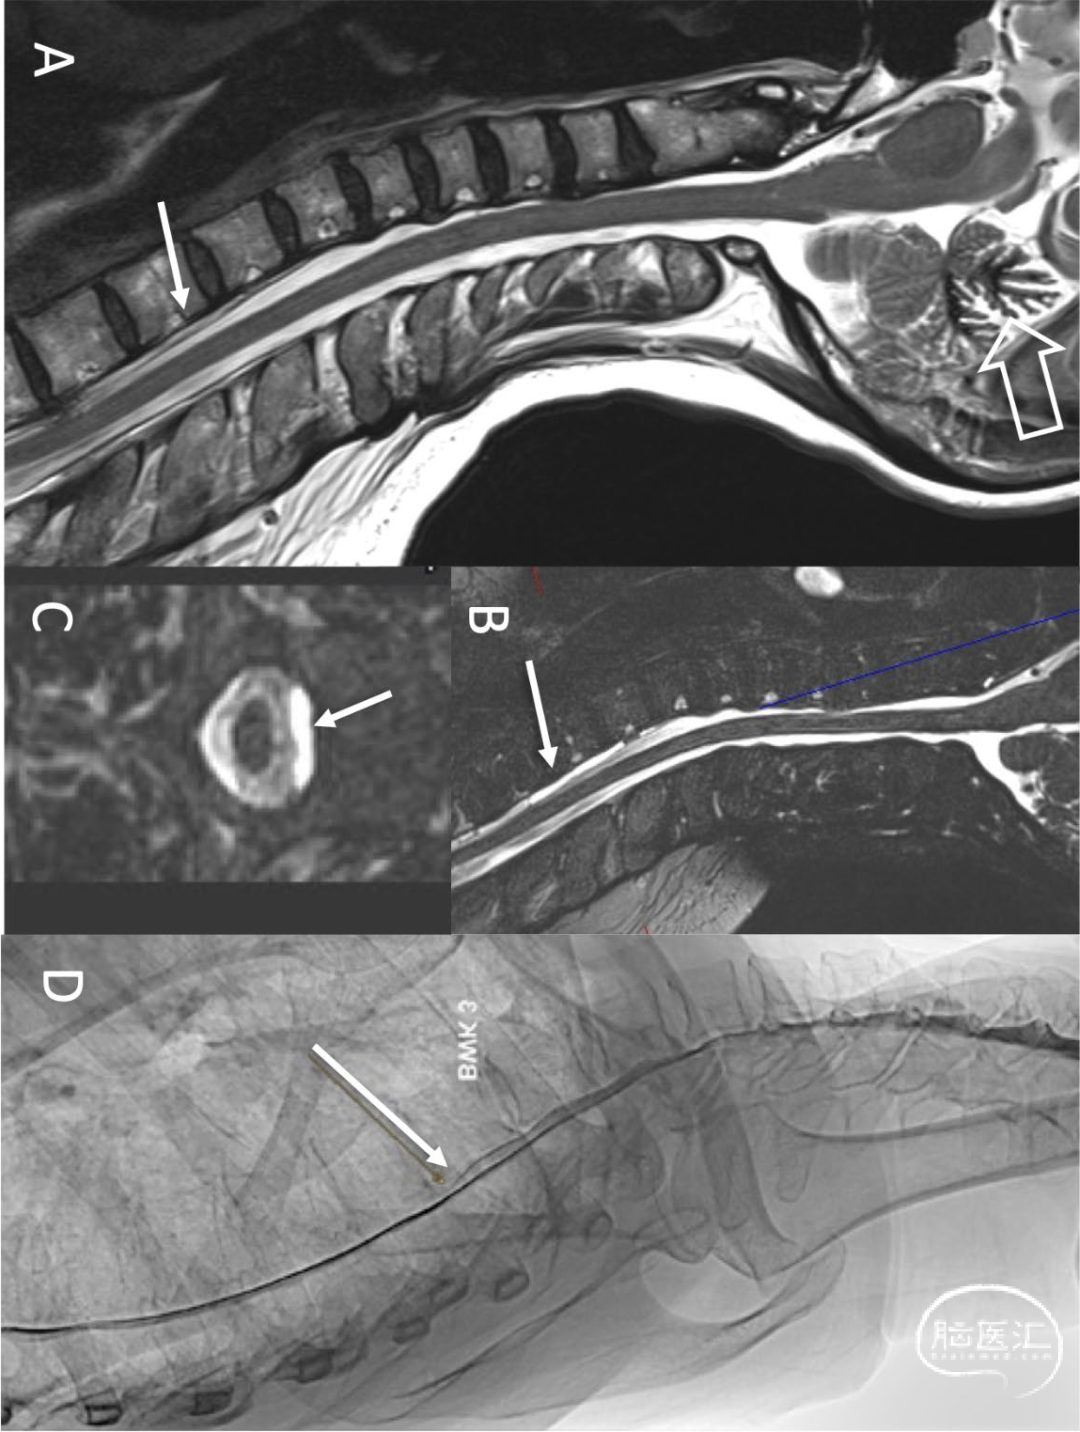

图4.女性,54岁。头痛、头压迫感、耳鸣、视力模糊、步态不稳和认知『慢』。颈椎矢状位T2加权MRI显示幕下含铁血黄素沉积症,上蚓叶含铁血铁血黄素(A:空心箭头)和脊髓纵向硬膜外积液(SLEC)(A:箭头)。heavily T2加权脂肪抑制SPACE序列可以计算脊髓腹侧大部分硬膜外积液(B,C:箭头)。高时间分辨率(1帧/秒)数字减影脊髓造影可见造影剂从蛛网膜下腔流出(D:箭头):